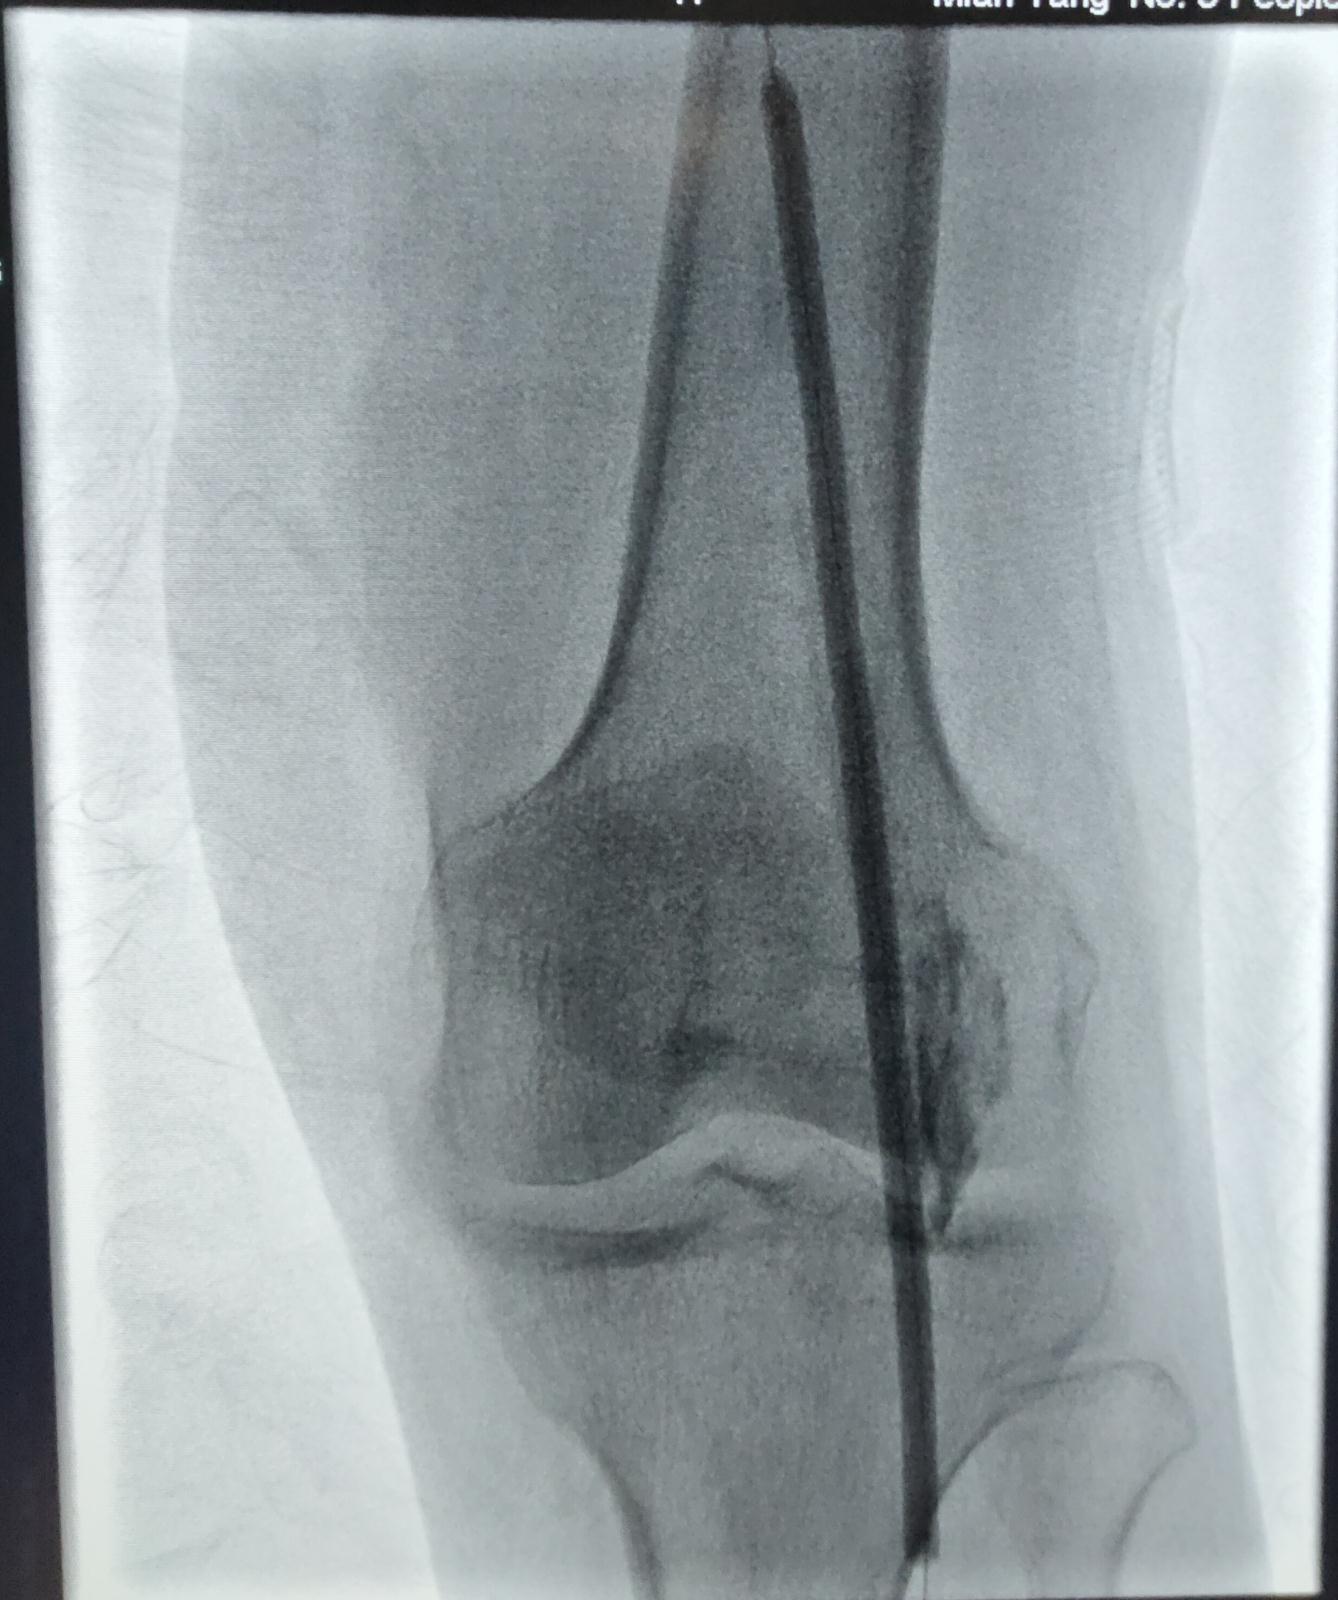

在介入科的最新DSA设备X线引导下,血管外科医生顺利将导丝导管送至病变部位,完成腹主动脉和双下肢血管造影。血管的整体走形和病变形态在西门子的zee ceiling血管机上被清晰的显示。DSA精确测量病变血管直径、长度,完美辅助医生选取合适的球囊和支架,最终顺利完成髂外动脉、股浅动脉、腘动脉的球囊扩张,并植入支架。

▲ 图为术中用球囊扩张腘动脉